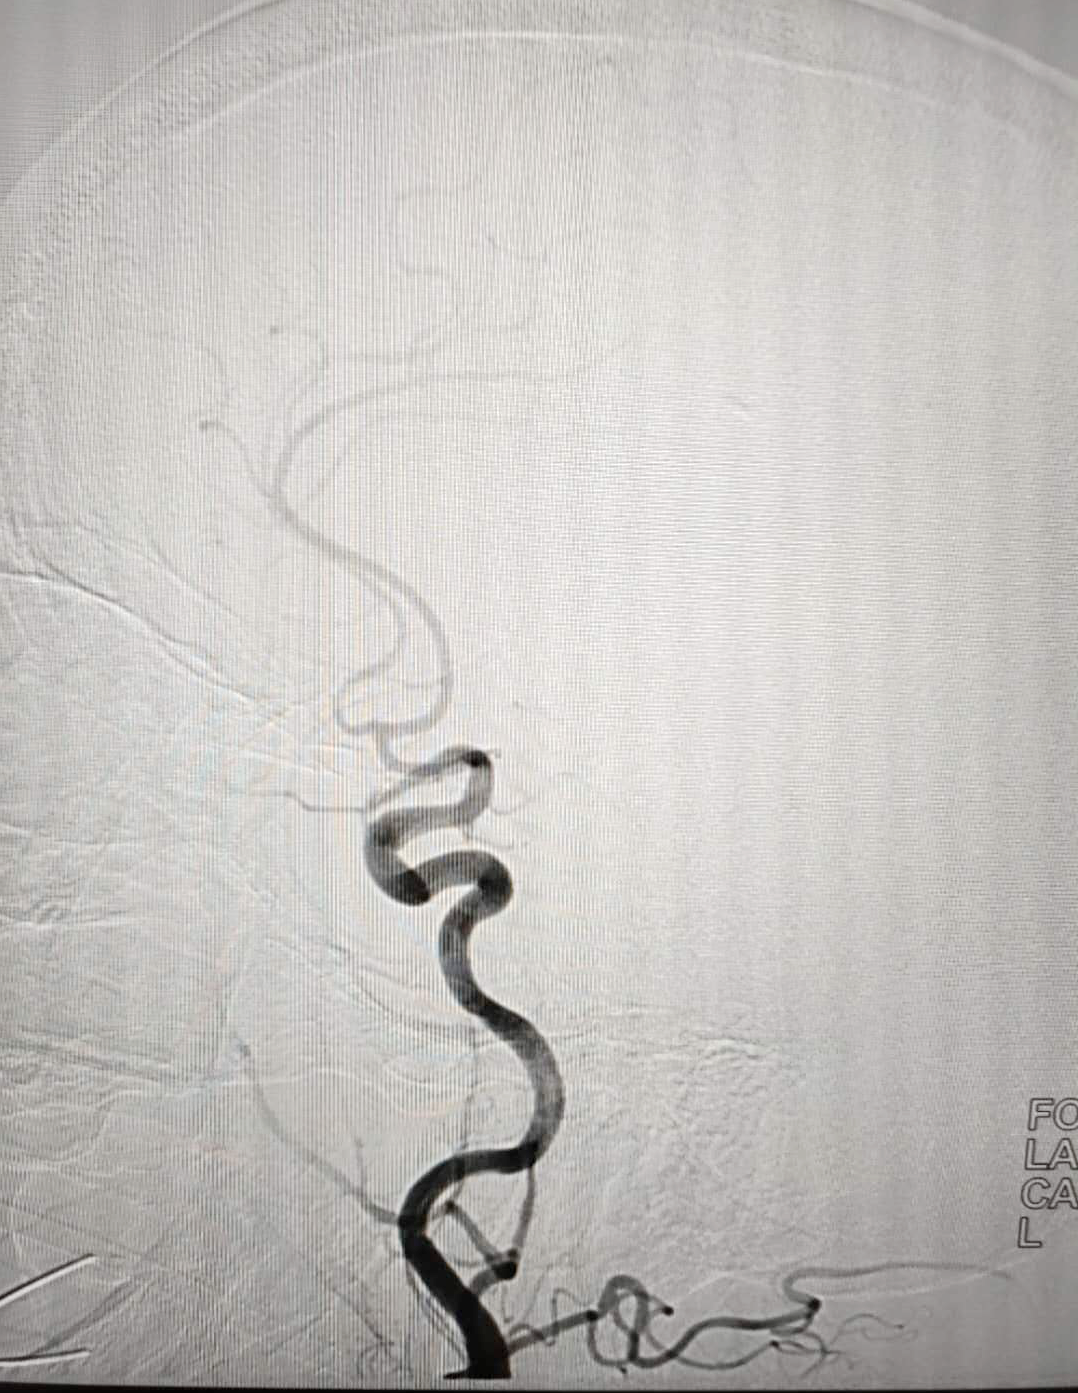

治疗脑梗塞主要有溶栓和取栓两种方式。对取栓而言,有相对较长的时间窗,即发病到开始取栓的时间段,最长可达24小时,但最好是控制在6小时之内,这样才能获得最好的治疗效果,而患者的发病时间恰好在这个时间范围内,为取栓赢得了宝贵的手术机会。经过积极的准备后,手术在康宏达主任的指导下,由脑血管病介入团队冉军民、姜正辕、卢永强主治医师顺利完成。术后,患者的右侧大脑中动脉开通,血流恢复,TICI 3级,NIHSS评分10分,症状改善,手术取得圆满成功。

▲左为抽取出的血栓,右为取栓术后造影

此次手术的成功标志着我院能够承担陇南市及周边地区急性缺血性卒中的急救任务,神经外科二病区此次率先独立自主完成神经介入血管内治疗,实现了甘肃南部地区神经介入领域之前仅仅能做造影检查到现在能够完成血管内治疗,从外请专家指导到独立自主完成的历史性跨越,也标志着今后我院能够给缺血性卒中脑血管病患者提供更优质规范的诊疗服务。